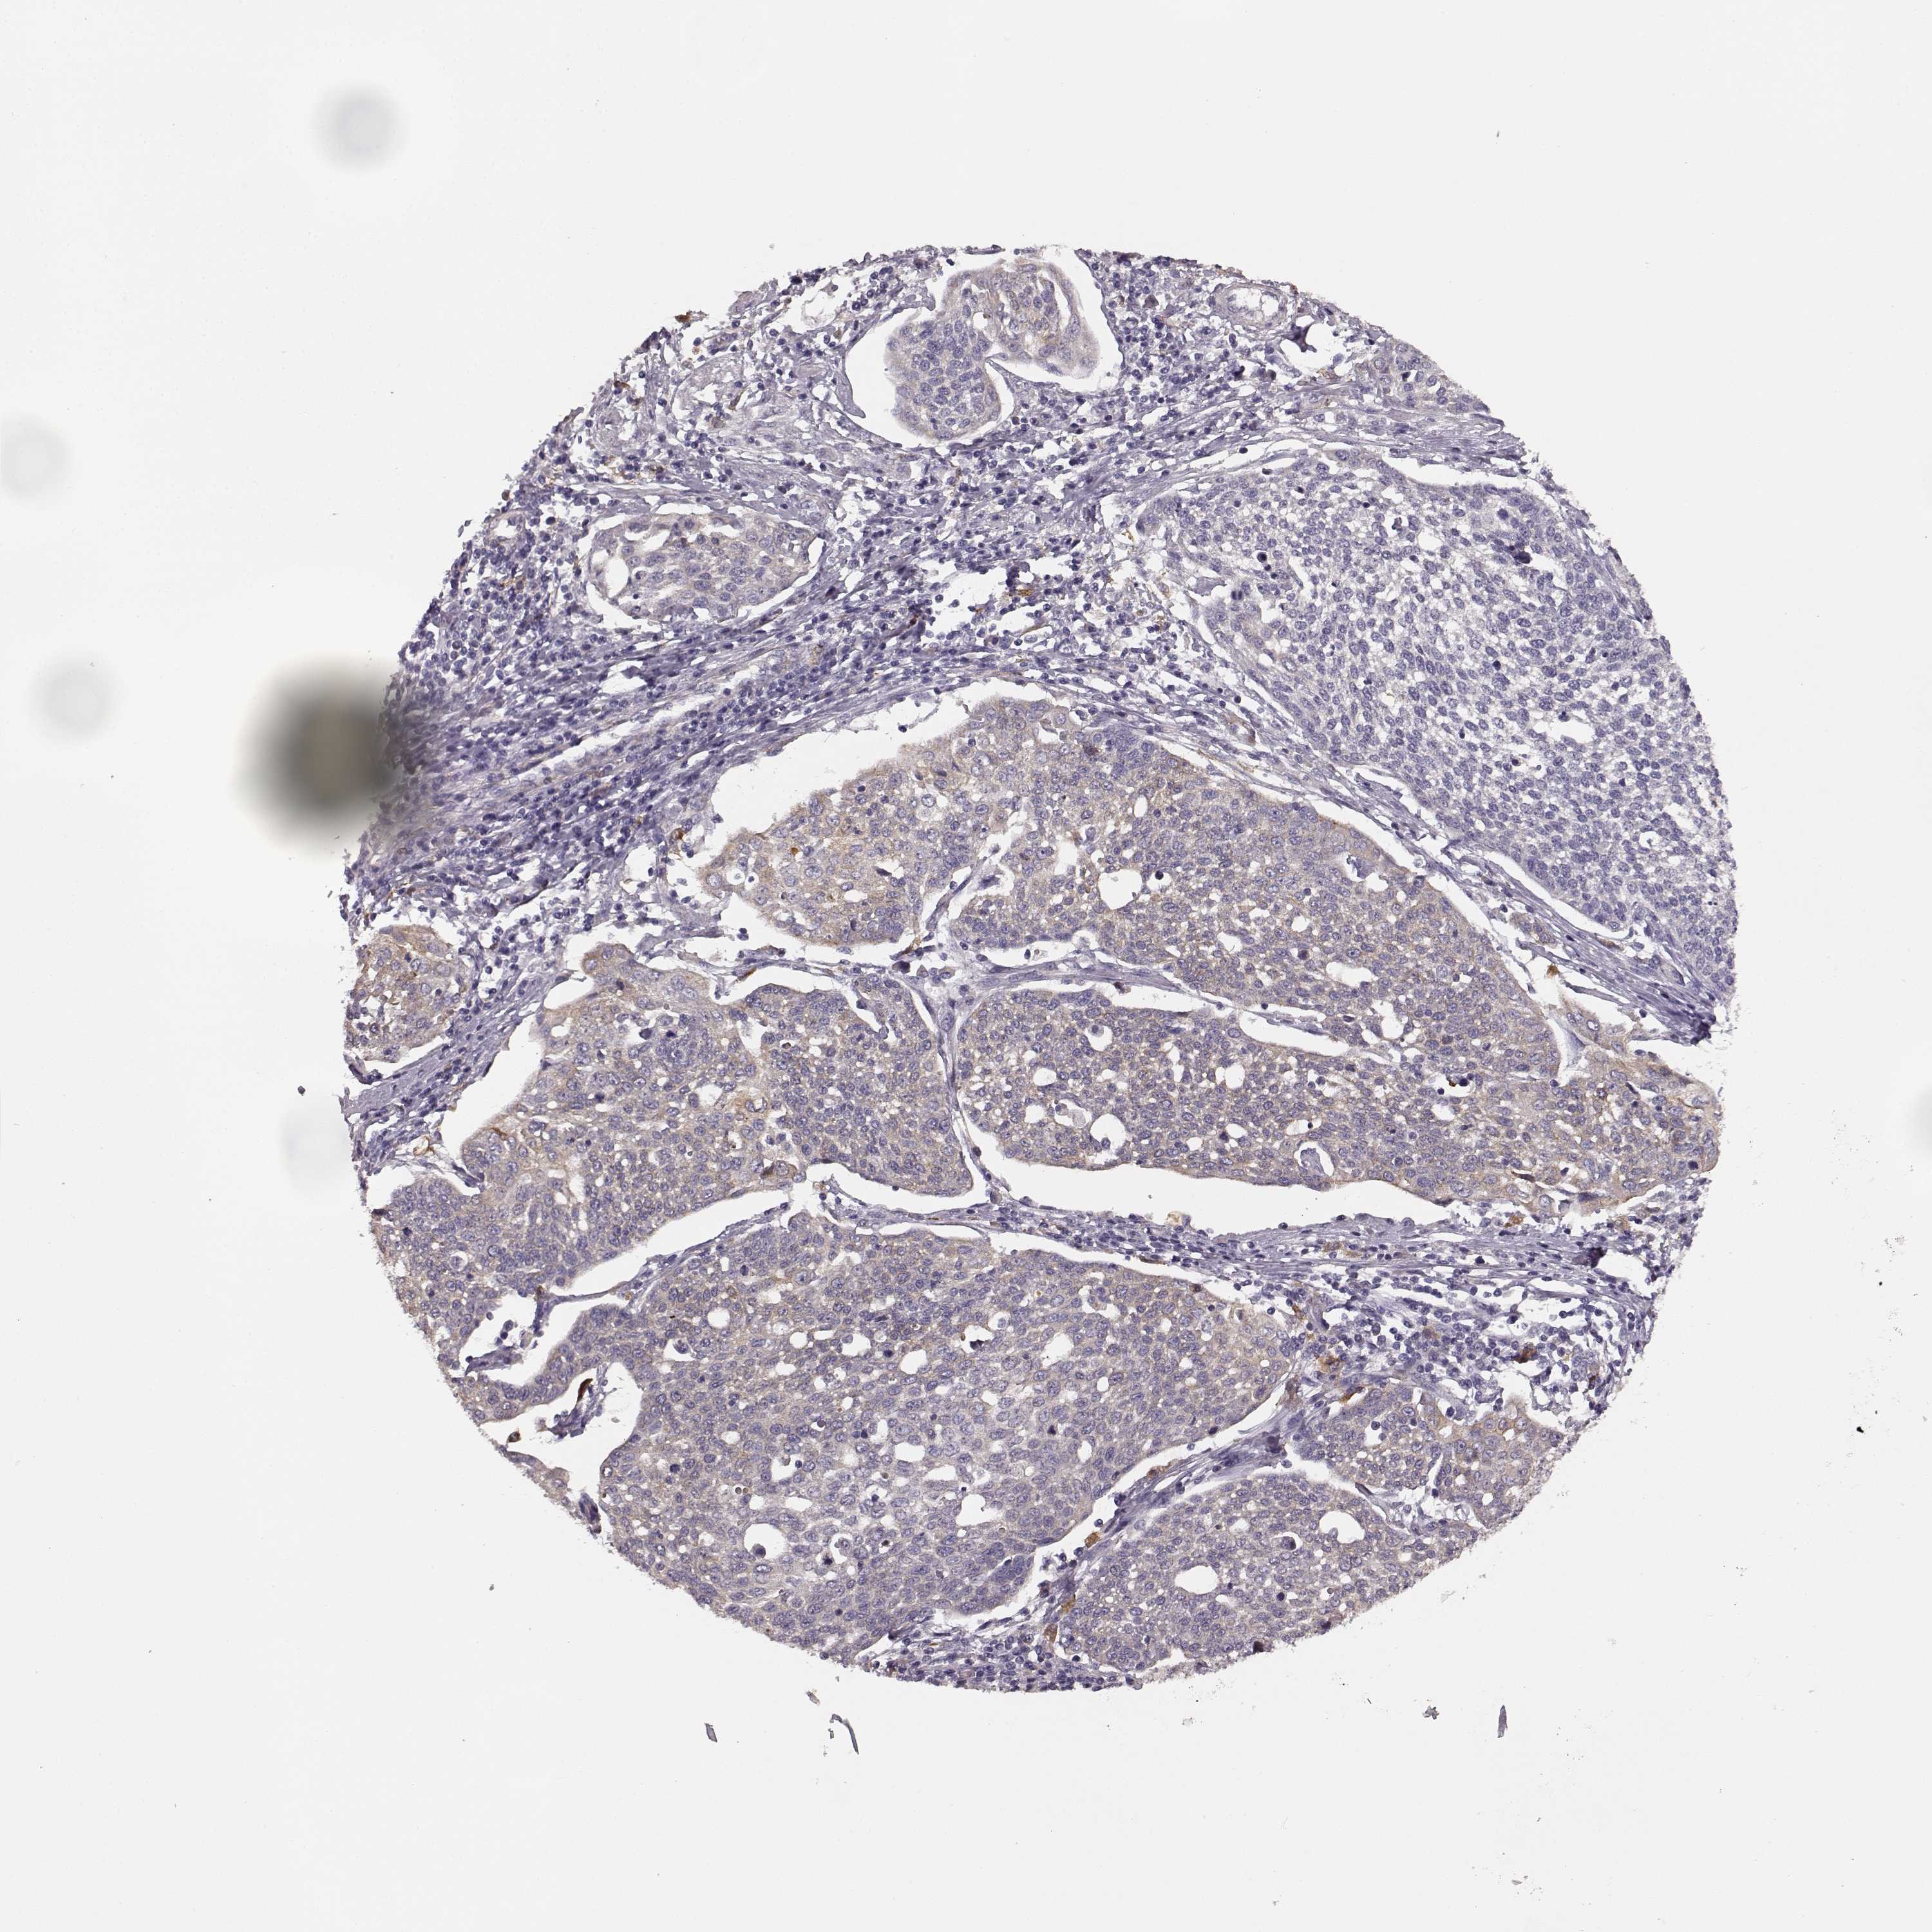

CERVICAL CANCER - Protein expressioni

A mouse-over function shows sample information and annotation data. Click on an image to view it in a full screen mode. Samples can be filtered based on level of antibody staining by selecting one or several of the following categories: high, medium, low and not detected. The assay and annotation is described here.

Note that samples used for immunohistochemistry by the Human Protein Atlas do not correspond to samples in the TCGA dataset.

Antibody stainingi

Antibody staining in the annotated cell types in the current human tissue is reported as not detected, low, medium, or high, based on conventional immunohistochemistry profiling in selected tissues. This score is based on the combination of the staining intensity and fraction of stained cells.

Each image is clickable and will lead to virtual microscopy that enables deeper exploration of all samples and also displays staining intensity scores, fraction scores and subcellular localization as well as patient and tissue information for each sample.

Antibody HPA045339

Staining

High

Medium

Low

Not detected

Intensity

Strong

Moderate

Weak

Negative

Quantity

>75%

75%-25%

<25%

None

Location

Nuclear

Cytoplasmic/membranous

Cytoplasmic/membranous,nuclear

Squamous cell carcinoma, NOS

Adenocarcinoma, NOS